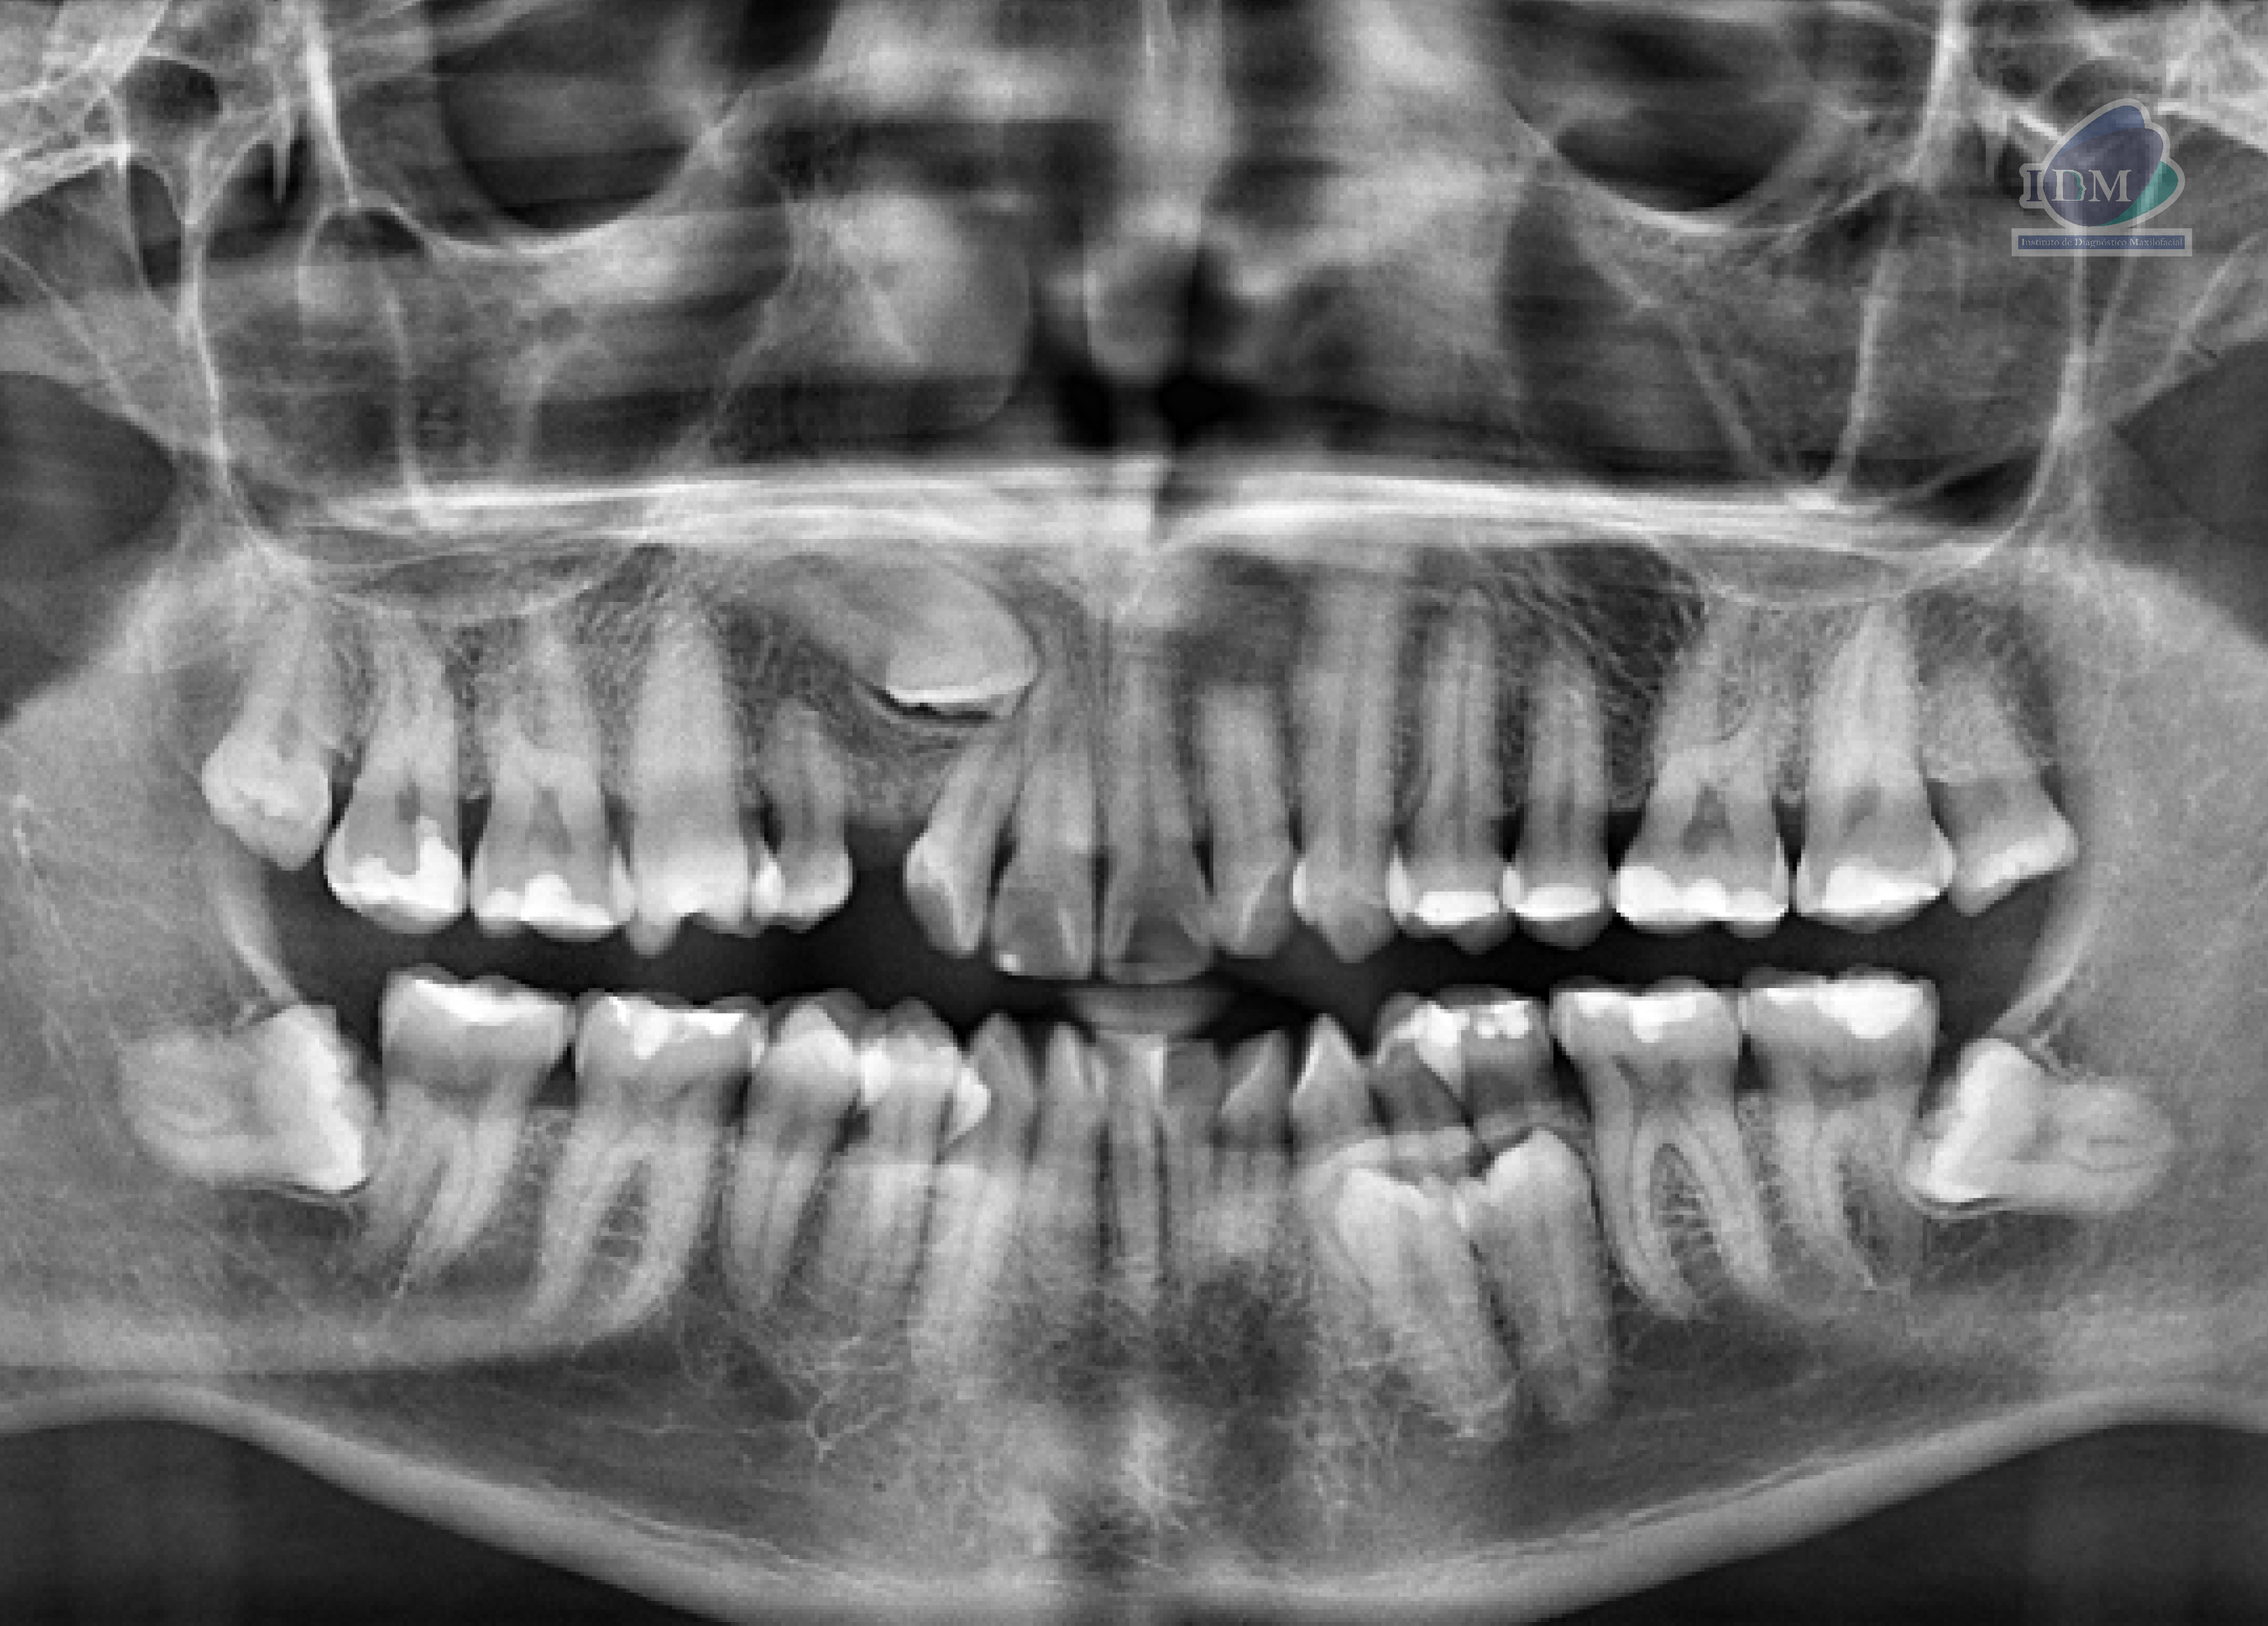

Paciente masculino de 29 años acude para una tomografía computarizada para una evaluación general. A la evaluación de la radiografía panorámica se observa la neumatización de ambos senos maxilares. la impactación de la pieza 23, múltiples piezas con material restaurador, la sobreproyección de las piezas 14 y 15, la presencia de una microdiente supernumerario en zona de pieza 14, la presencia de dos supernumerarios intraóseos en el tercer cuadrante y la presencia de dos supernumerarios extraóseos en el cuarto cuadrante, así como las piezas 38 y 48 impactadas hacia mesial.

Radiografia Panorámica